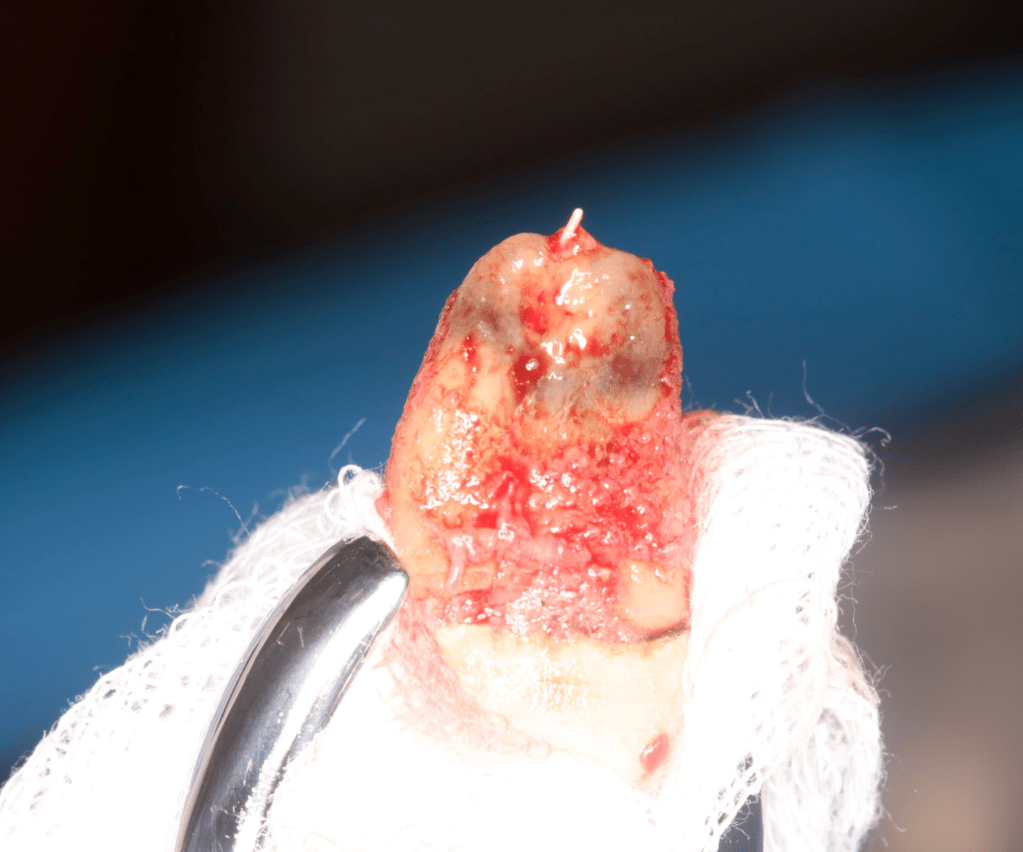

Reimplante, istmo apical, curación cortical palatina 1 año